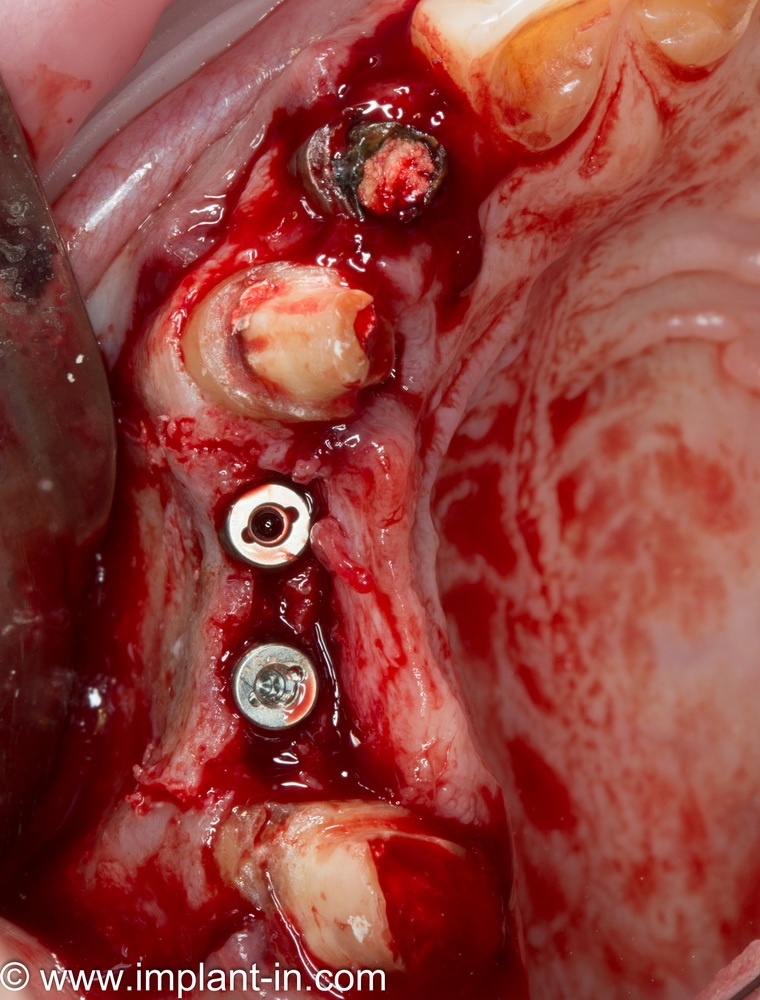

или имплантацией

Откроем область операции и посмотрим, что там:

Вроде как, всё неплохо. Наверное, можно поставить имплантаты?

ну, или как-то так:

При этом, я хотел бы обратить ваше внимание на один важный момент. То, с чем вы сейчас работаете — не кость, в привычном нам гистолого-физиологическом понимании. Это костная мозоль вперемежку с графтом. Её свойства довольно сильно отличаются от того, что мы привыкли называть костной тканью. Поэтому при установке имплантатов соблюдайте максимальную осторожность и щадящий режим. Никаких диких торков, усилий, больших переходов между размерами фрез допускать нельзя. Будьте аккуратны.